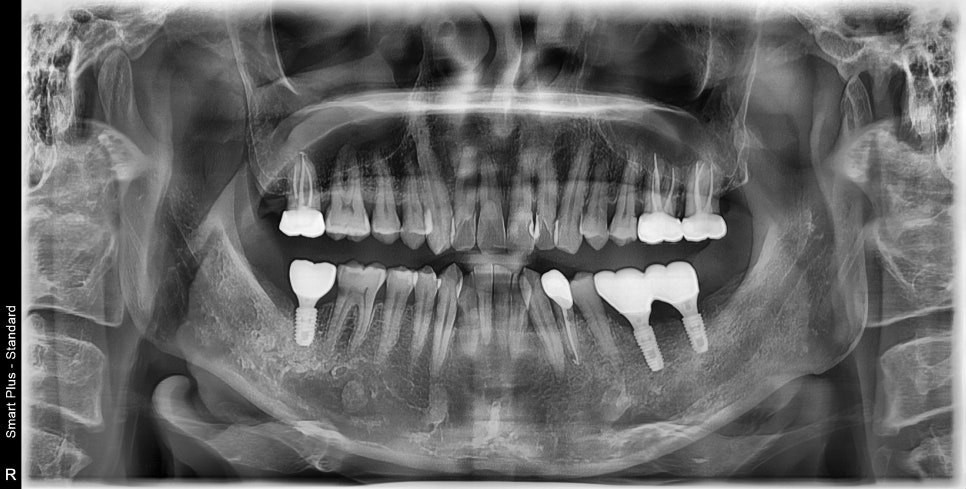

상실된 어금니 부위는 임플란트가 필요하고 해당 부위

말고도 앞니 쪽으로 다발성 우식이 생긴 상태고, 부위에 따라서 신경치료의 가능성이 큰 치아들도 보입니다.

치아의 상실 기간이 길어지게 되면 반대편 치아들이 정출되고

임플란트 식립 후 과거의 이상적인 교합을 만들어 주기 위해서는 의도적으로 크라운 치료를 해야 하며

치아의 정출 양에 따라서 신경치료도 동반해야 하는 경우가 생깁니다.

먼저 시간이 오래 걸리는 임플란트부터 심었습니다.

염증이 심했던 뿌리를 제거한 곳은 임플란트 식립과 동시에 뼈이식으로 같이 하고 잇몸 안에 묻어놓은 상태입니다.

임플란트 본을 뜰 시기에 맞춰 많이 정출되어 있는 치아들을 의도적으로 신경치료 후 보철 치료까지 진행하였습니다.

모든 보철 치료까지 끝난 후의 사진입니다.